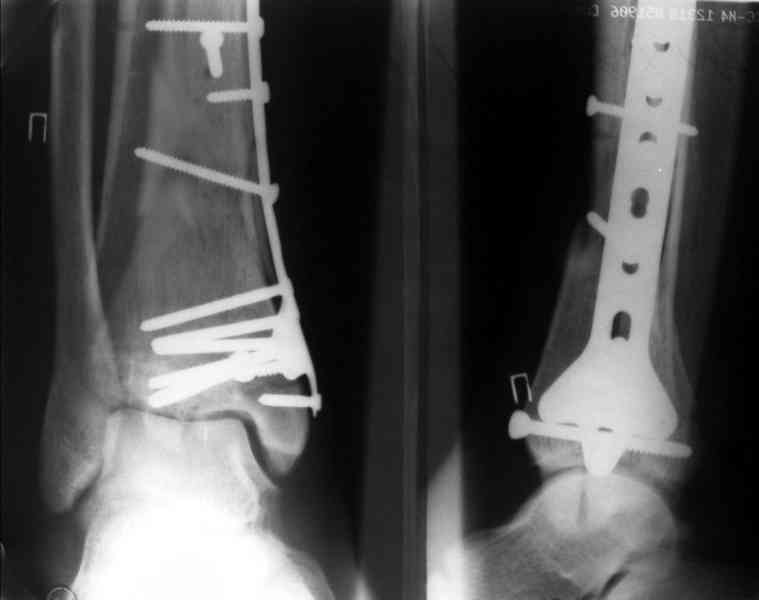

Это типичный перелом пилона, который надп лечить только открыто.Извини те что опоздал к обсуждению, но даже если вы уже оперировали больного по Илизарову это даже лучше.Посылаю картинки.

Дрягин

Посмотрим вроде прошло если понравится напишите расскажу как это сделать.По принципам АО кстати при поступлении сначала восстанавливают длину малоберцовой кости фиксируют пластиной 1/3 трубки потом накладывают аппарат наружной фиксации и через 7-10 дней открыто восстанавливают большеберцовую кость.С уважением Дрягин

На рентгенограммах типичный перелом пилона по типу С-3. есть опыт до 100 открытых опреаций у нас в клинике. 20 примерно в год. Принцип один -все внутрисуставные переломы нуждаются в открытой репозиции и внутренней стабильной фиксации. При поступлении КТ не надо, так как получается только нагромождение костей. Истинной картины нет. Главное восстановить длину малоберцовой кости - это ключ к успеху. При поступлении меньше всего надо думать о сосудистых расстройствах, т.к. сама операция и репозиция даже сначала частичная даёт улучшение сосудитых нарушений. Причём очень быстро. Операция в 2этапа. При поступлении доступ позади наружной лодыжки, причём обязательно. После этого репозиция малоберцовой кости и фиксация пластиной 1/3 трубки под винт 3,5. Дренаж и любой аппарат наружной фиксации. Затем после спадения отёка на 5-7-10 день аппрат снимается и дугообразный разрез спереди от медиальной лодыжки 10-12 см. Главной чтобы расстояние между 1 и вторым разрезом было не меньше 7-8 см. Тогда не будет некрозов лоскутов. Таранная кость используется как матрица на неё укладываются отломки и фиксируются пицами. Ренг-контроль. Отломки лежат все отдельно, но ничего не высыпется. При переломах С-3 всегда нужна костная пластика (из крыла). Фиксация пластиной лист клевера простой или LCP. Гипс не нужен. Дренаж до 48 часов. Операция длится 3-4 часа обязательно без жгута. Посылаю примерно такой же случай.